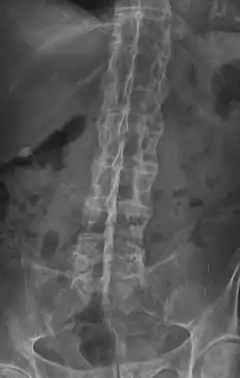

| تغیر شکل بامبو در پرتونگاری ستون فقرات. | |

علائم بالینی شامل خشکی صبحگاهی، گاهی اوقات آرتریت التهابی مفاصل زانو و هیپ و سایر مفاصل، خم شدن سر و گردن بیمار به جلو و ایراد در راست نگهداشتن سر و گردن، وتب خفیف میباشند. در تست شوبر از محاذات ستیغ خاصره در پایین کمر نقطهای علامتگذاری میشود و ۱۰ سانتیمتر بالاتر از آن نقطه دیگری علامتگذاری میشود، سپس از بیمار خواسته میشود به جلو خم شود و در این حالت مجدداً فاصله بین این دو نقطه اندازهگیری میشود در فرد سالم این فاصله از ۱۳ سانتیمتر بیشتر خواهد بود (تست شوبر منفی) در حالیکه در فرد مبتلا به التهاب مهره خمیده، این فاصله از ۱۳ سانتیمتر بیشتر نخواهد شد (تست شوبر مثبت). در رادیوگرافی روبروی ستون فقرات و ناحیه خاجی-تهیگاهی حالت منحصربهفردی در موارد پیشرفته بیماری دیده میشود که در آن جسم مهرهها از طرفین به یکدیگر متصل شدهاند (ستون مهرهای خیزرانی bamboo spine). در آزمایش خون نیز در موارد حاد بیماری افزایش ESR و CRP را داریم. آنتیبادیHLA-B27 در خون بیش از ۹۰٪ بیماران وجود دارد.